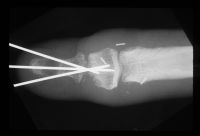

| Temporary pin placement. |

| After tapping the bone graft into place. |